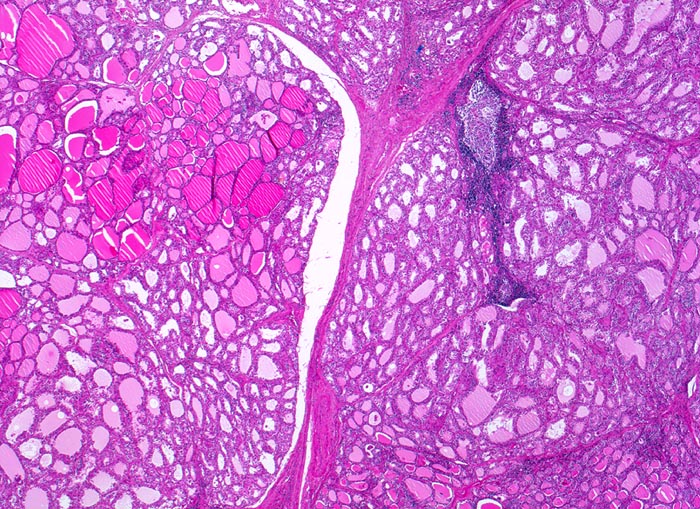

Zwischen den einzelnen Schilddrüsenläppchen verlaufen schmale Bindegewebssepten. Vereinzelt sind Lymphfollikel mit Keimzentren vorhanden. Das Parenchym ist auffallend inhomogen. Neben hormonell wenig aktiven grossen Follikeln mit flachem Epithel und dunklem Kolloid finden sich zahlreiche Follikel mit Zeichen der gesteigerten hormonellen Aktivität: hochprismatisches Epithel, helles oder fehlendes Kolloid.

Das Vorhandensein von hormonell wenig aktiven Follikeln mit reichlich Kolloid beruht möglicherweise auf der vorausgegangenen thyreostatischen Therapie.